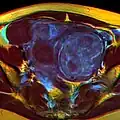

A very large (9 cm) fibroid of the uterus which is causing pelvic congestion syndrome as seen on CT

-